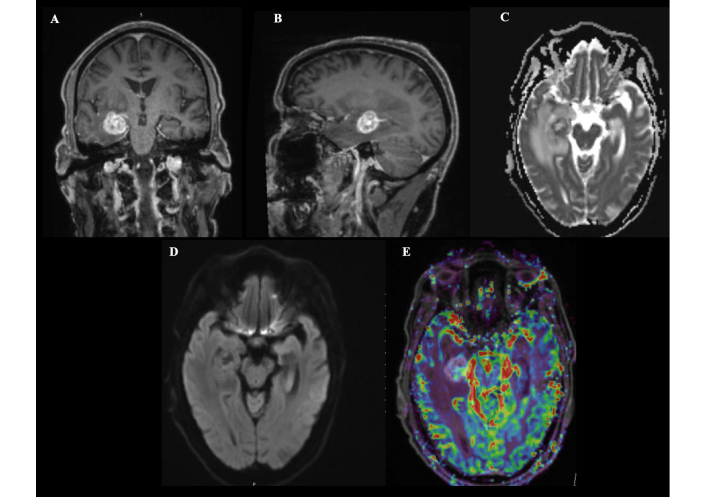

A 64-year-old male with a medical history significant for hypertension, a prior complicated left femoral fracture managed with hardware removal and a Girdlestone procedure, and a recent episode of extended-spectrum beta-lactamase (ESBL)-producing urosepsis was admitted for evaluation of a right temporal brain lesion. He initially presented with progressive confusion. Magnetic resonance imaging (MRI) revealed a right medial temporal lobe intra-axial lesion with associated vasogenic edema and midline shift, with a differential diagnosis including lymphoma, tuberculoma, or abscess (Figure 1).

Preoperative magnetic resonance imaging findings of a right temporal lobe lesion. Magnetic resonance imaging reveals a well-defined, rounded lesion in the deep medial right temporal lobe measuring approximately 20 mm × 18 mm × 20 mm (anteroposterior × transverse × craniocaudal) (A: coronal; B: sagittal). The lesion demonstrates contrast enhancement and is surrounded by significant vasogenic edema, causing mass effect on the temporal horn and mild compression of the adjacent basal cistern, without significant midline shift (C). Diffusion-weighted imaging shows peripheral restriction with central facilitation (D), and perfusion imaging reveals increased cerebral blood volume, suggestive of a high-grade lesion (E).